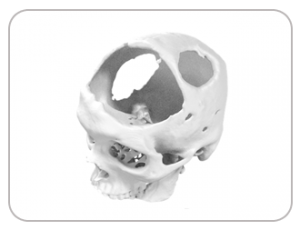

” Intracerebral Hemorrhage patient gets a new lease of life with ExaFITT PMMA implant “

Mr. Deep, a high school student was traumatized due to deformity in his head as a result of Intracerebral Hemorrhage (ICH). He had to loose a sizable chunk of his skull due to the condition and had to remain highly cautious to protect the exposed part. Medicad was able to deliver the precision fit ExaFITT PMMA implant within industry best of 4 days time.

DEFECT FROM HEAD INJURY

DESIGNED IMPLANT

IMPLANT FABRICATED WITH PMMA